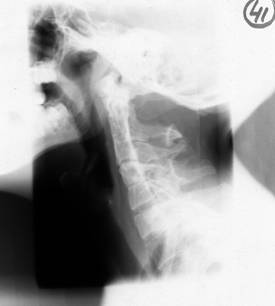

Fig. 93 – Fractura - luxatie cervicala